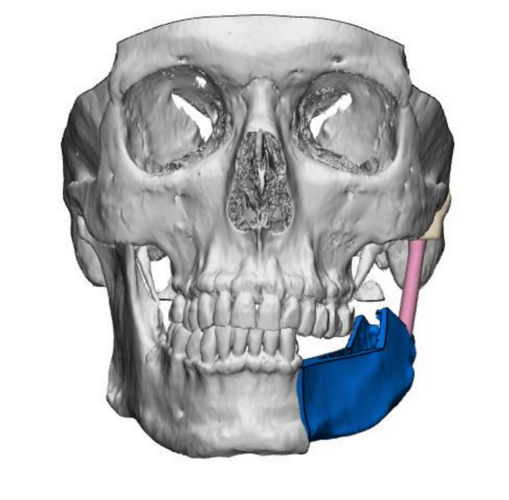

One of the most complex surgeries performed in the clinic involved the reconstruction of the temporomandibular joint using a 3D-printed alloplastic material. This procedure also included the application of a custom-designed iliac crest osteomyocutaneous flap, harvested with the aid of an individualized template. This innovative approach significantly enhances treatment options for patients with craniofacial cancers, substantially improving their quality of life.